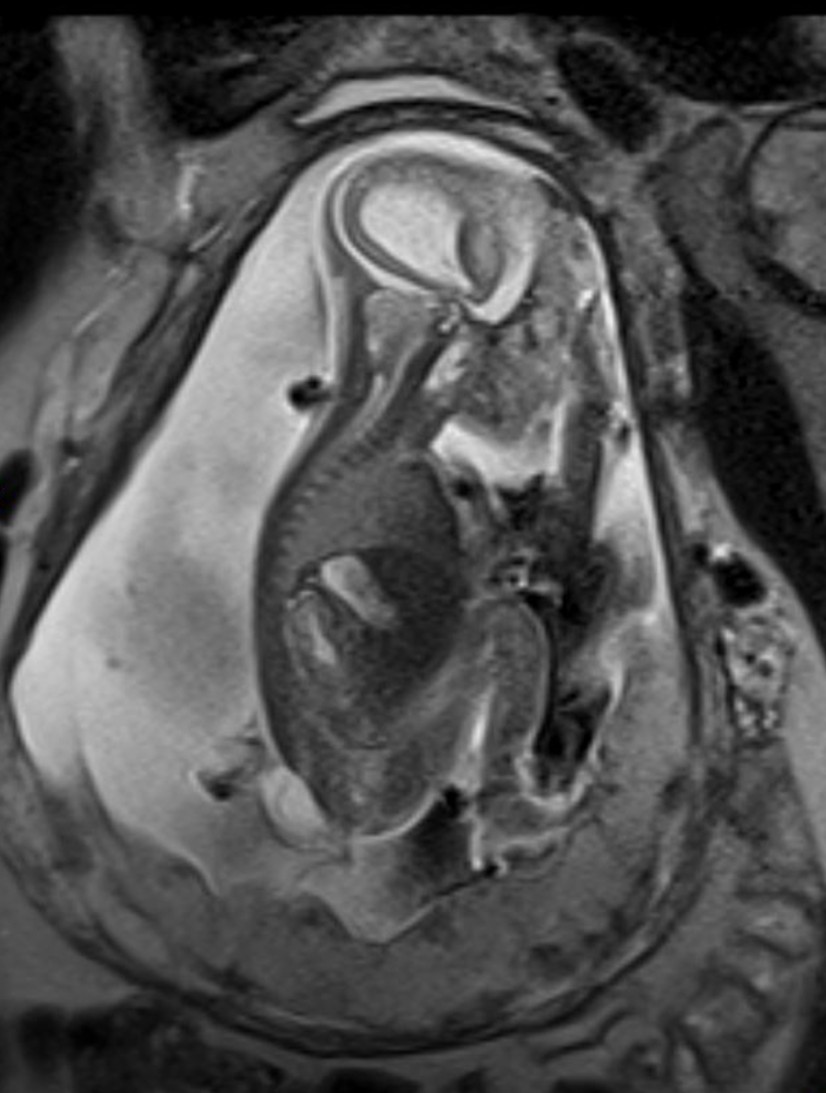

Das fetale MRT (Magnetresonanztomographie) ist ein strahlungsfreies Verfahren, mit dem wir Organe und Strukturen Ihres ungeborenen Kindes besonders detailreich darstellen. Es ergänzt die pränatale Ultraschall-Diagnostik und hilft, Fragestellungen präzise zu klären und die weitere Betreuung zu planen.

- Abklärung von Auffälligkeiten im Ultraschall, z. B. Gehirn, Wirbelsäule, Lunge, Bauchorgane

- Beurteilung von Organreife und Entwicklung, wenn die Sicht im Ultraschall eingeschränkt ist (z. B. mütterlicher Body-Mass-Index, Lage des Kindes)

Unsere Neuroradiologen arbeiten eng mit Pränatalmedizinern, Neonatologen, Pädiatern und Chirurgen zusammen. Modernste Geräte und spezialisierte Protokolle sorgen für hohe Bildqualität – auch bei kindlichen Bewegungen.